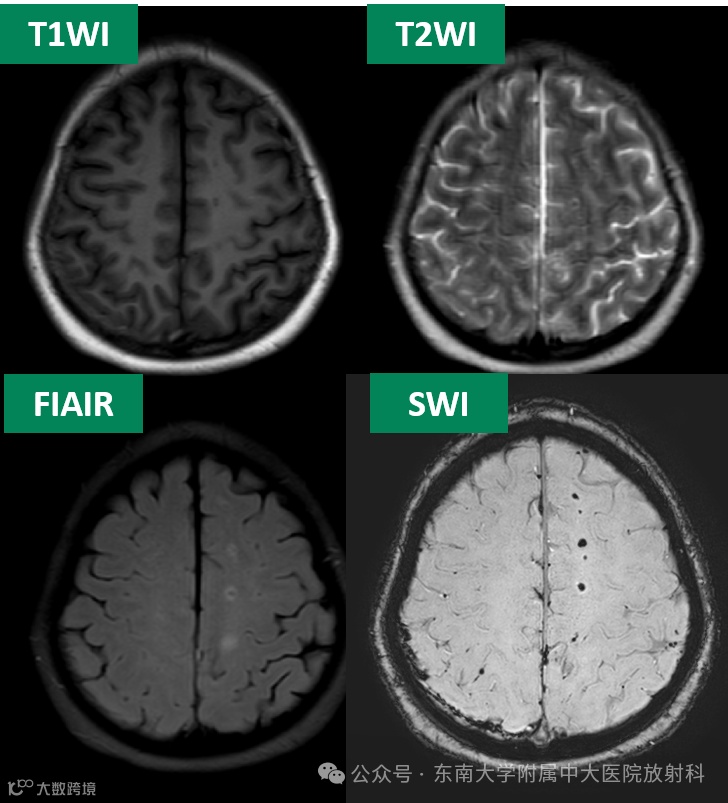

主诉:外伤后意识障碍 4 小时 -

病史:4小时前患者骑电动车时摔倒,当即出现昏迷由120送至我院江北院区,入急诊时呈昏迷状态,瞳孔左侧瞳孔6mm,右侧瞳孔2mm,对光反射消失。查体不配合。家属为求进一步就诊,转至我院本部

影像学表现